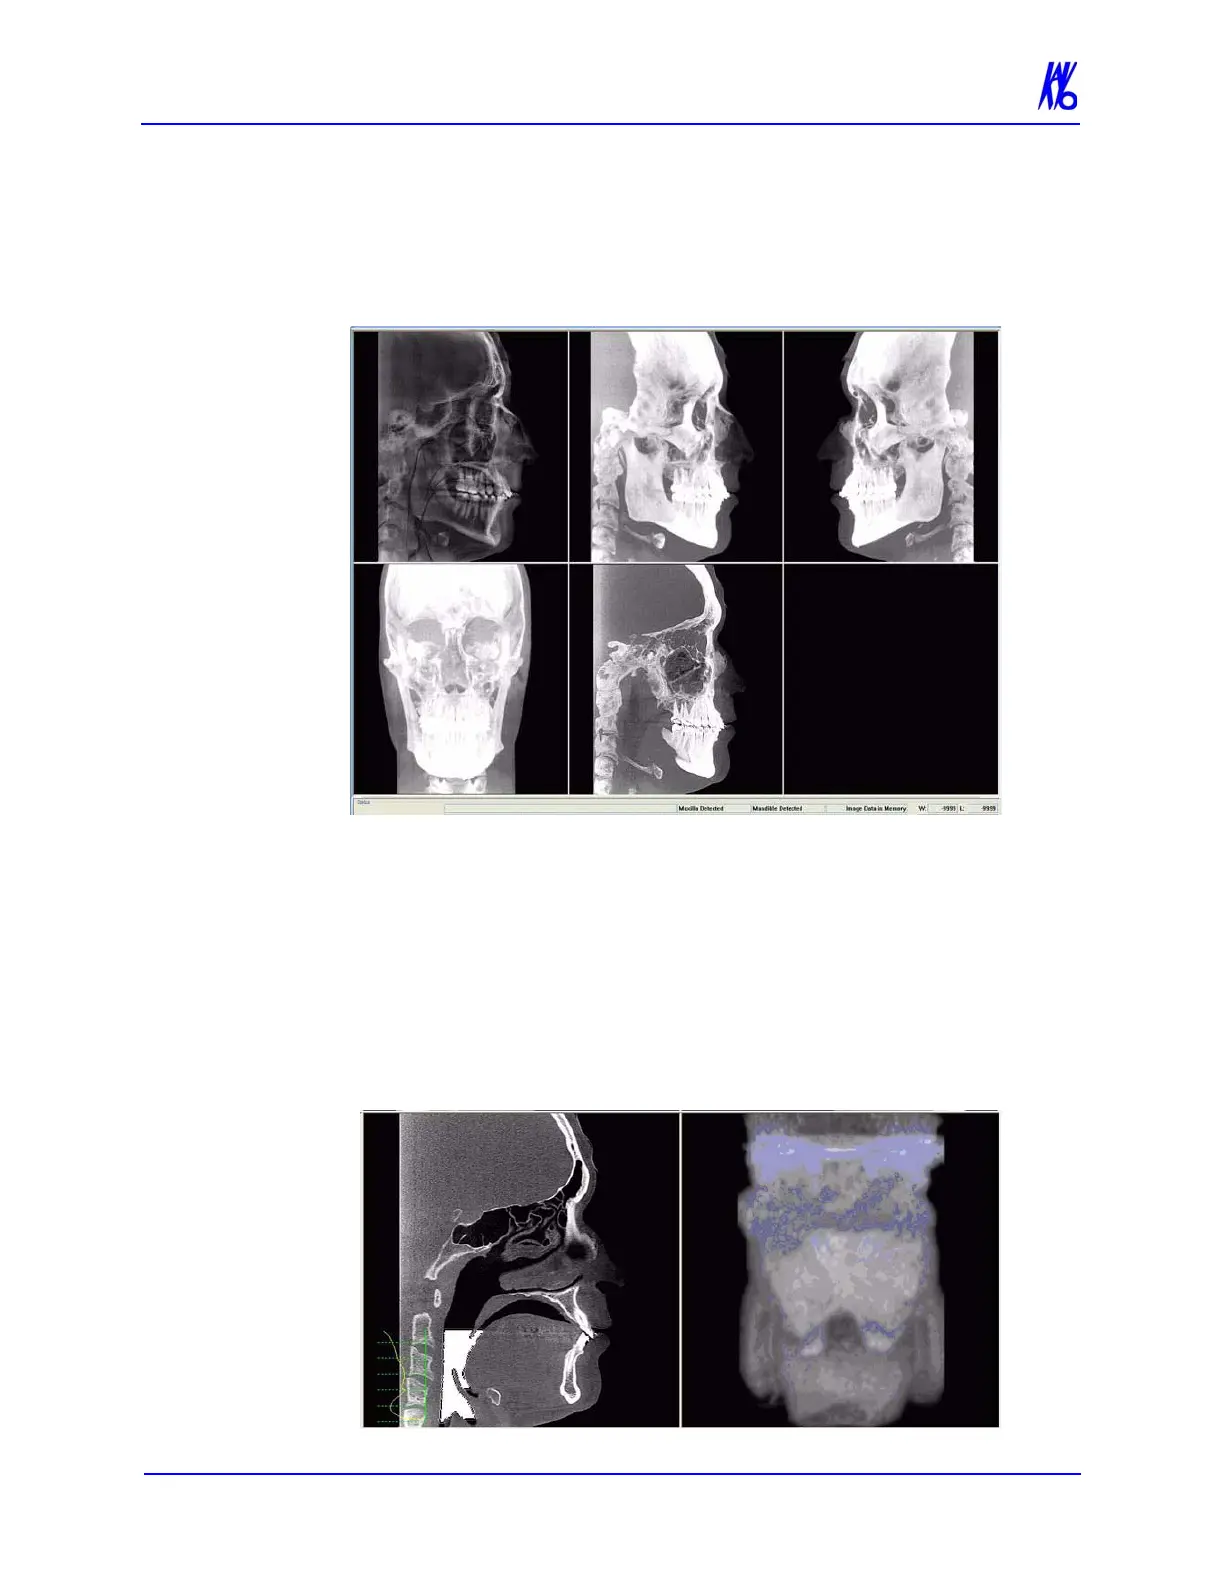

Ceph Screen

Double-clicking the Sagittal View on the Preview Screen displays

the Ceph Screen.

The Ceph screen displays the Lateral Cephs in Radiographic and

MIP mode as well as a Coronal View in MIP mode, all at the

thickness of the volume. The last image is a Mid Sagittal Slice at

20mm thick.

Right-clicking the blank view at the bottom right of the Ceph screen

displays a single item popup menu. Clicking Tag Airways generates

a 3D view of the airways for the patient in the blank view. In

addition, the tagged airway data is graphed in the view at the bottom

center of the Ceph screen.